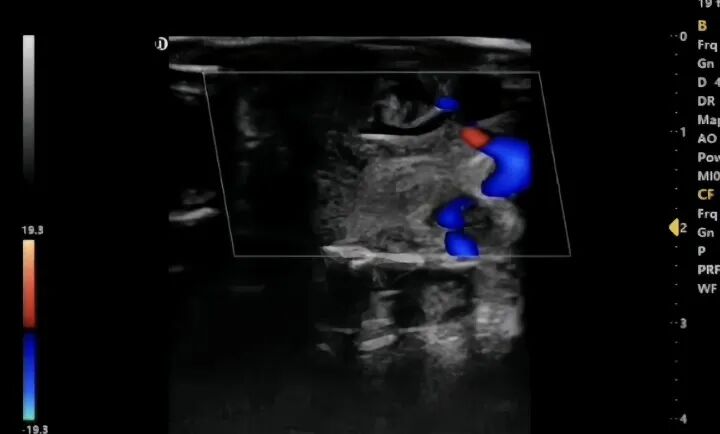

A research institute in Yunnan called, expressing their interest in having Dawei Veterinary Medical demonstrate the use of the L3-VET laptop-style veterinary color Doppler ultrasound for examining the gonads of Chinese giant salamanders. Since the animals are relatively small, we will use the linear array probe we provide.